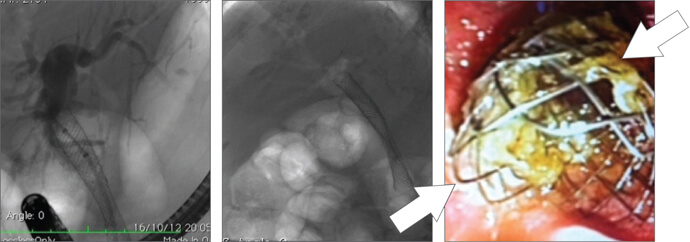

Case 3

An 80-year-old patient was admitted with previous diagnoses of pancreatic cancer. In June 2012, ERCP with ST the first 60 mm Evolution Biliary uncovered stent was placed. Approximately 5 months later, the patient was admitted with jaundice and tumor ingrowth into the stent lumen. During a second ERCP, a second Evolution Biliary uncovered stent (80 mm) was placed.